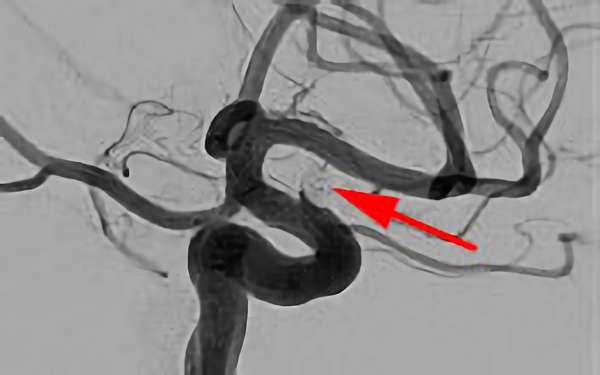

No.1631 手術中